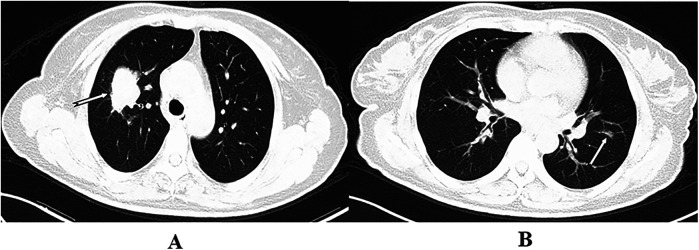

Background and objective: The increased use of chest CT for clinical diagnosis and screening has improved the detection of early-stage lung cancer and the identification of bilateral lung lesions. Despite this, consensus on the feasibility of simultaneous vs. staged bilateral surgery for patients with bilateral lesions remains elusive, necessitating further investigation. This study assessed the safety, feasibility, and health-economics value of simultaneous bilateral pulmonary surgery by comparing perioperative clinical indicators and medical costs with those of unilateral surgery and simulated staged bilateral surgery.

Methods: A retrospective analysis was conducted using clinical data from 78 patients who underwent simultaneous bilateral pulmonary surgery at the Lung Cancer Center of West China Hospital of Sichuan University by the same medical team from January 2016 to October 2024. An equal number of patients who underwent unilateral surgery during the same period served as controls. Perioperative indicators were compared between these groups, and medical expenses were assessed against those of a second control group undergoing simulated staged surgery.